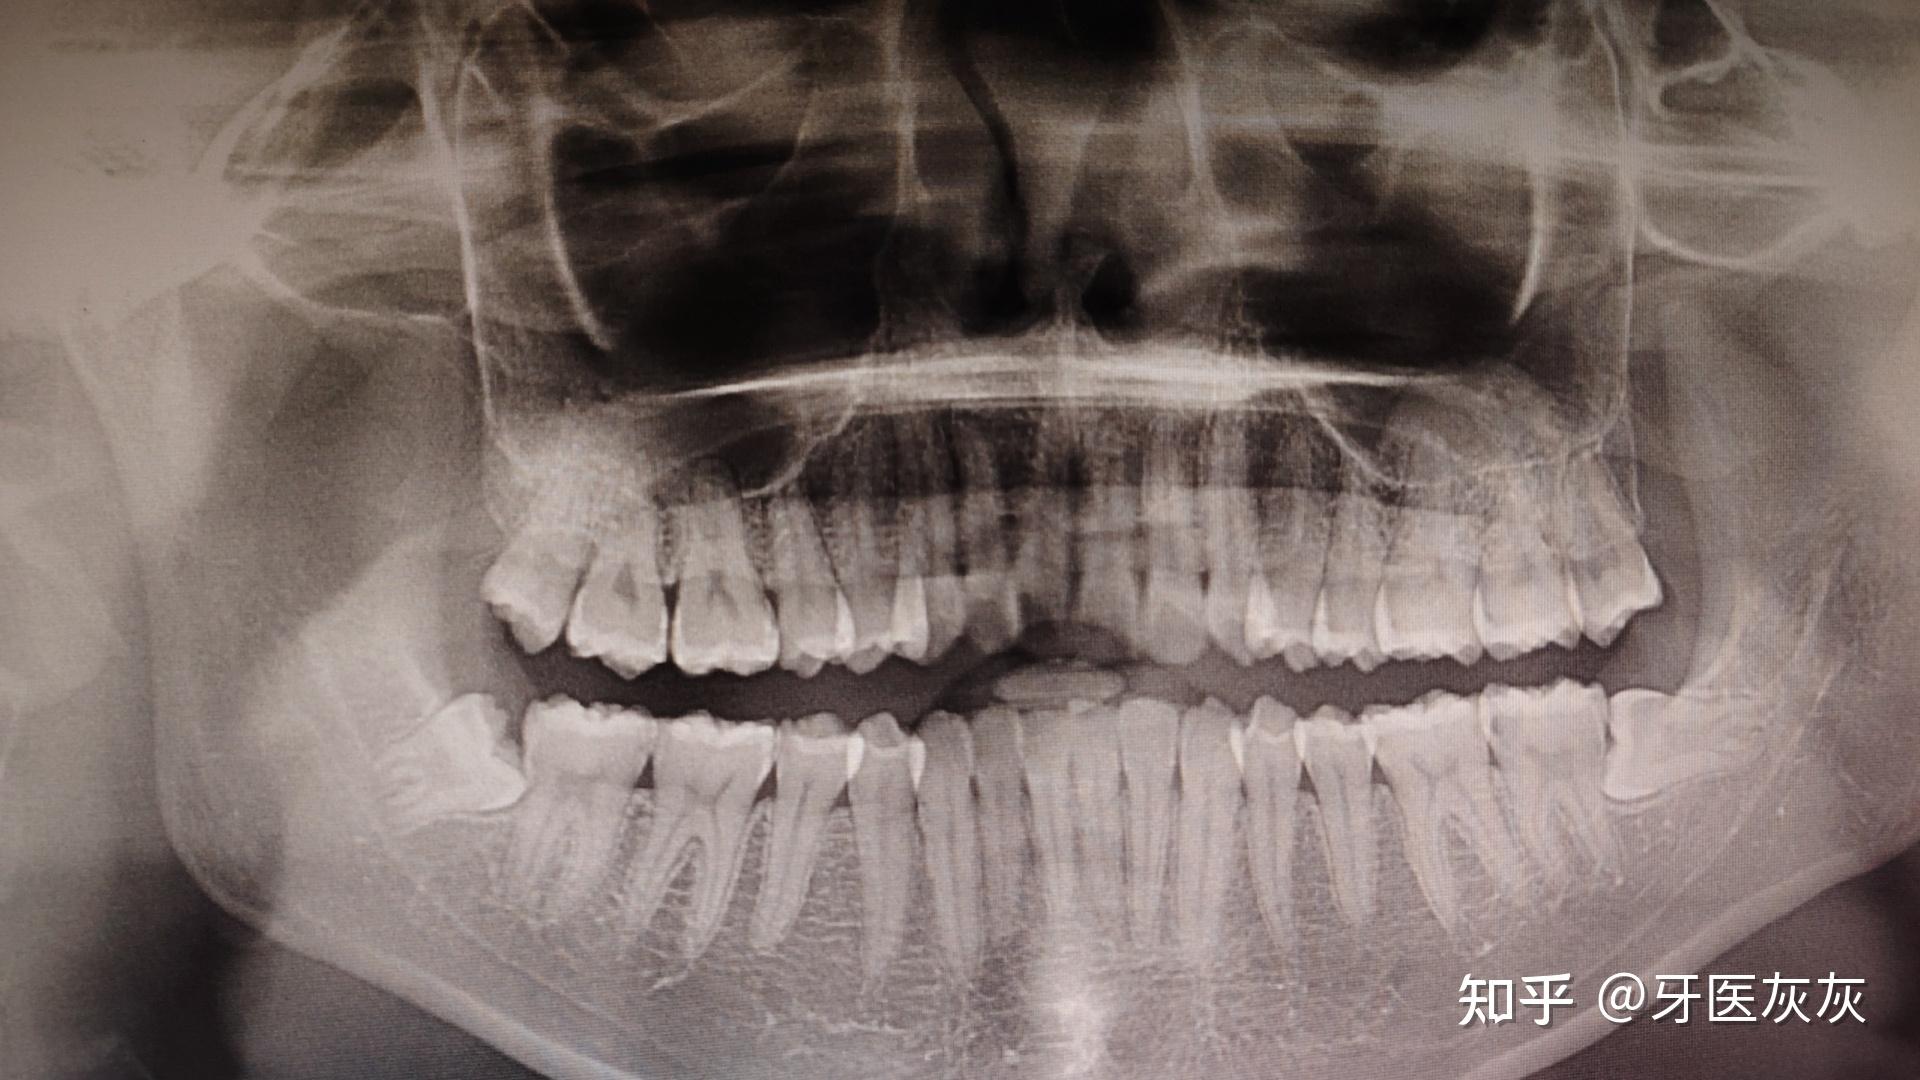

拔一个阻生齿大概多少钱

拔除阻生智齿的费用因牙齿情况不同而有所差异,以下是具体费用说明上颌阻生智齿拔除费用大概是200元上颌埋伏阻生智齿拔除费用大概是500元下颌阻生智齿拔除费用大概是元下颌埋伏阻生智齿拔除费用大概是1000元左右注意以上费...